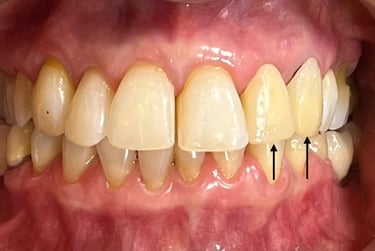

Coroas em Dissilicato de Lítio

Todos os caso a seguir estão associadas a clareamento dentário

Cirurgia de aumento de coroa clínica antes das coroas

Caso que demonstra a vantagem da integração de diversas áreas da odontologia, unindo cirurgia, periodontia, prótese e estética para alcançar resultados funcionais e harmônicos.

Antes

Depois